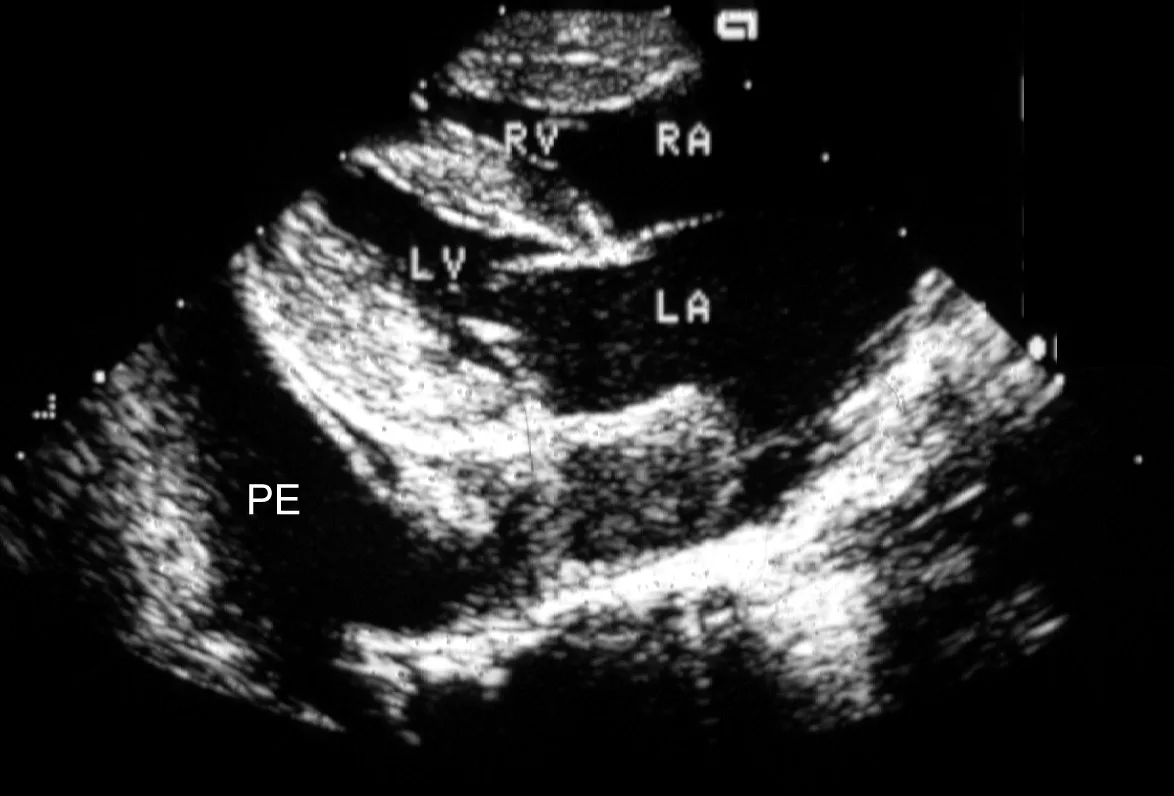

Once the patient is stabilized (often after 12 to 24 H), obtain radiographs (Figure 3) and echocardiography to confirm the diagnosis of CHF and to identify the nature and severity of the cardiac disease. The most common cause of CHF in cats is HCM; less common are dilated, restrictive, and unclassified cardiomyopathy. Murmurs associated with HCM are usually created by mitral regurgitation, abnormal displacement of the mitral valve during systole (systolic anterior motion or SAM), causing left ventricular outflow tract obstruction, or dynamic right ventricular obstruction either in combination (e.g., mitral regurgitation is always present with SAM) or alone (mitral regurgitation can also occur without SAM) (Figure 4).

FIGURE 4A Two-dimensional, right parasternal, long-axis view of the heart in a cat with HCM and pleural effusion. Note the large thrombus in the left atrium